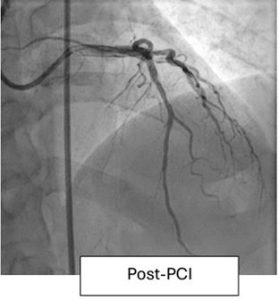

Chandigarh PGI: पीजीआई चंडीगढ़ में पहली बार विदेशी मशीन पेनम्ब्रा कैट आरएक्स (Penumbra CAT Rx) की मदद से एक ह्दयरोगी का सफल इलाज किया गया। इस मशीन की मदद ऐसे मरीजों के लिए ली जाती है जिनकी नसों के अंदर रक्त का थक्का जम जाता है और हार्ट फेल होने की संभावना होती है। इस मशीन की मदद से रक्त के थक्के को बाहर निकाला जाता है।

भारत में यह मशीन हाल ही में आई है। पीजीआई के कार्डियोलॉजिस्ट हिमांशु गुप्ता के नेतृत्व में डाक्टरों की टीम ने इस मशीन की मदद से 60 वर्षीय व्यक्ति की जान बचाई।

पीजीआई के कार्डियोलॉजिस्ट डॉक्टर हिमांशु गुप्ता के मुताबिक जिन मरीजों की नस में रुकावट की समस्या होती है। उन्हें स्टंट डालने की जरूरत पड़ती है।

उनके मुताबिक कई बार स्टंट डालने में नस के अंदर जमे खून के थक्के रुकावट बन जाते हैं, इसलिए इन्हें निकालना पड़ता है। इस मशीन की मदद से ऐसे थक्कों को आसानी से निकाला जा सकता है।

डॉ. गुप्ता ने बताया कि पहले हमारे पास केवल मैनुअल थ्रोम्बस एस्पिरेशन उपकरण थे जो बहुत प्रभावी नहीं थे। यह नया उपकरण वाहिकाओं से बड़े और यहां तक कि व्यवस्थित थ्रोम्बस को हटाने के लिए अधिक प्रभावी और कुशल है।